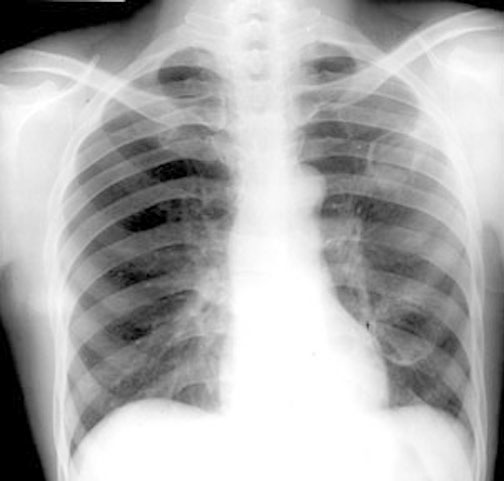

Case 1 Labeled Image What are the conditions where you get thin walled cavities?